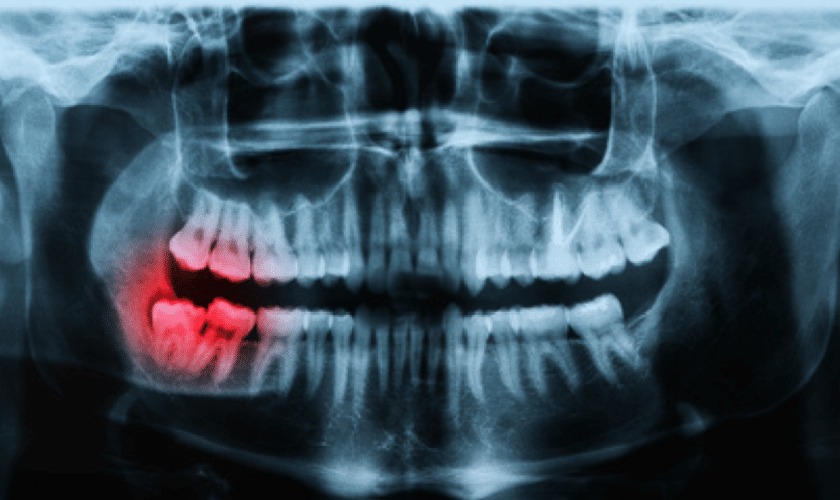

Before jumping into budgeting strategies, it’s vital to understand what you’re planning for. A panoramic dental X-ray captures a 2D image of the entire mouth in a single shot, using minimal radiation. Unlike bitewing or periapical X-rays, which only show a section of your mouth, the panoramic version offers a broader and more comprehensive overview. It helps detect impacted teeth, jaw disorders, cysts, tumors, and even sinus issues.

Because of its broad diagnostic range, panoramic X-rays are often recommended for more complex or preventive dental assessments. This makes them a valuable tool, but also one that could come with a higher price tag compared to routine dental imaging.